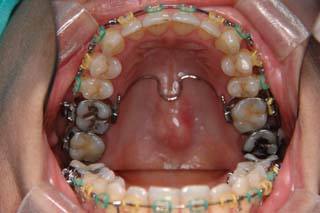

主訴:顎の歪み

診断名:骨格性下顎左方偏位

年齢:24歳

使用した主な装置名:TPB、マルチブラケット装置

抜歯/非抜歯および抜歯部位:非抜歯

治療期間:動的処置1年6か月、経過観察3年

費用の目安:保険適応 自己負担金として30~50万

リスク、副作用:外科手術によるリスク、マルチブラケット治療に伴う歯根吸収など偶発症が発生するリスクがある。

極めて強い側方変位を認めます。前後的・垂直的な問題は見られません。大きなズレであれば、外科的に骨のズレを改善する治療が選択されます。横断的な問題はその他の不正咬合と比較して、解決がかなり難しい事が多いです。治療後の後戻りが頻繁に見られる不正咬合ですので、外科矯正での改善が望ましい場合も多いでしょう。

このケースでは、外科手術は、上顎の傾斜の改善をLeFort1にて、下顎の正中の改善をSSROにて行いました。